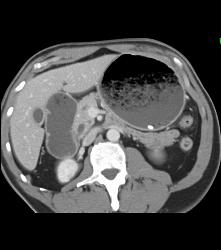

GIST Tumor